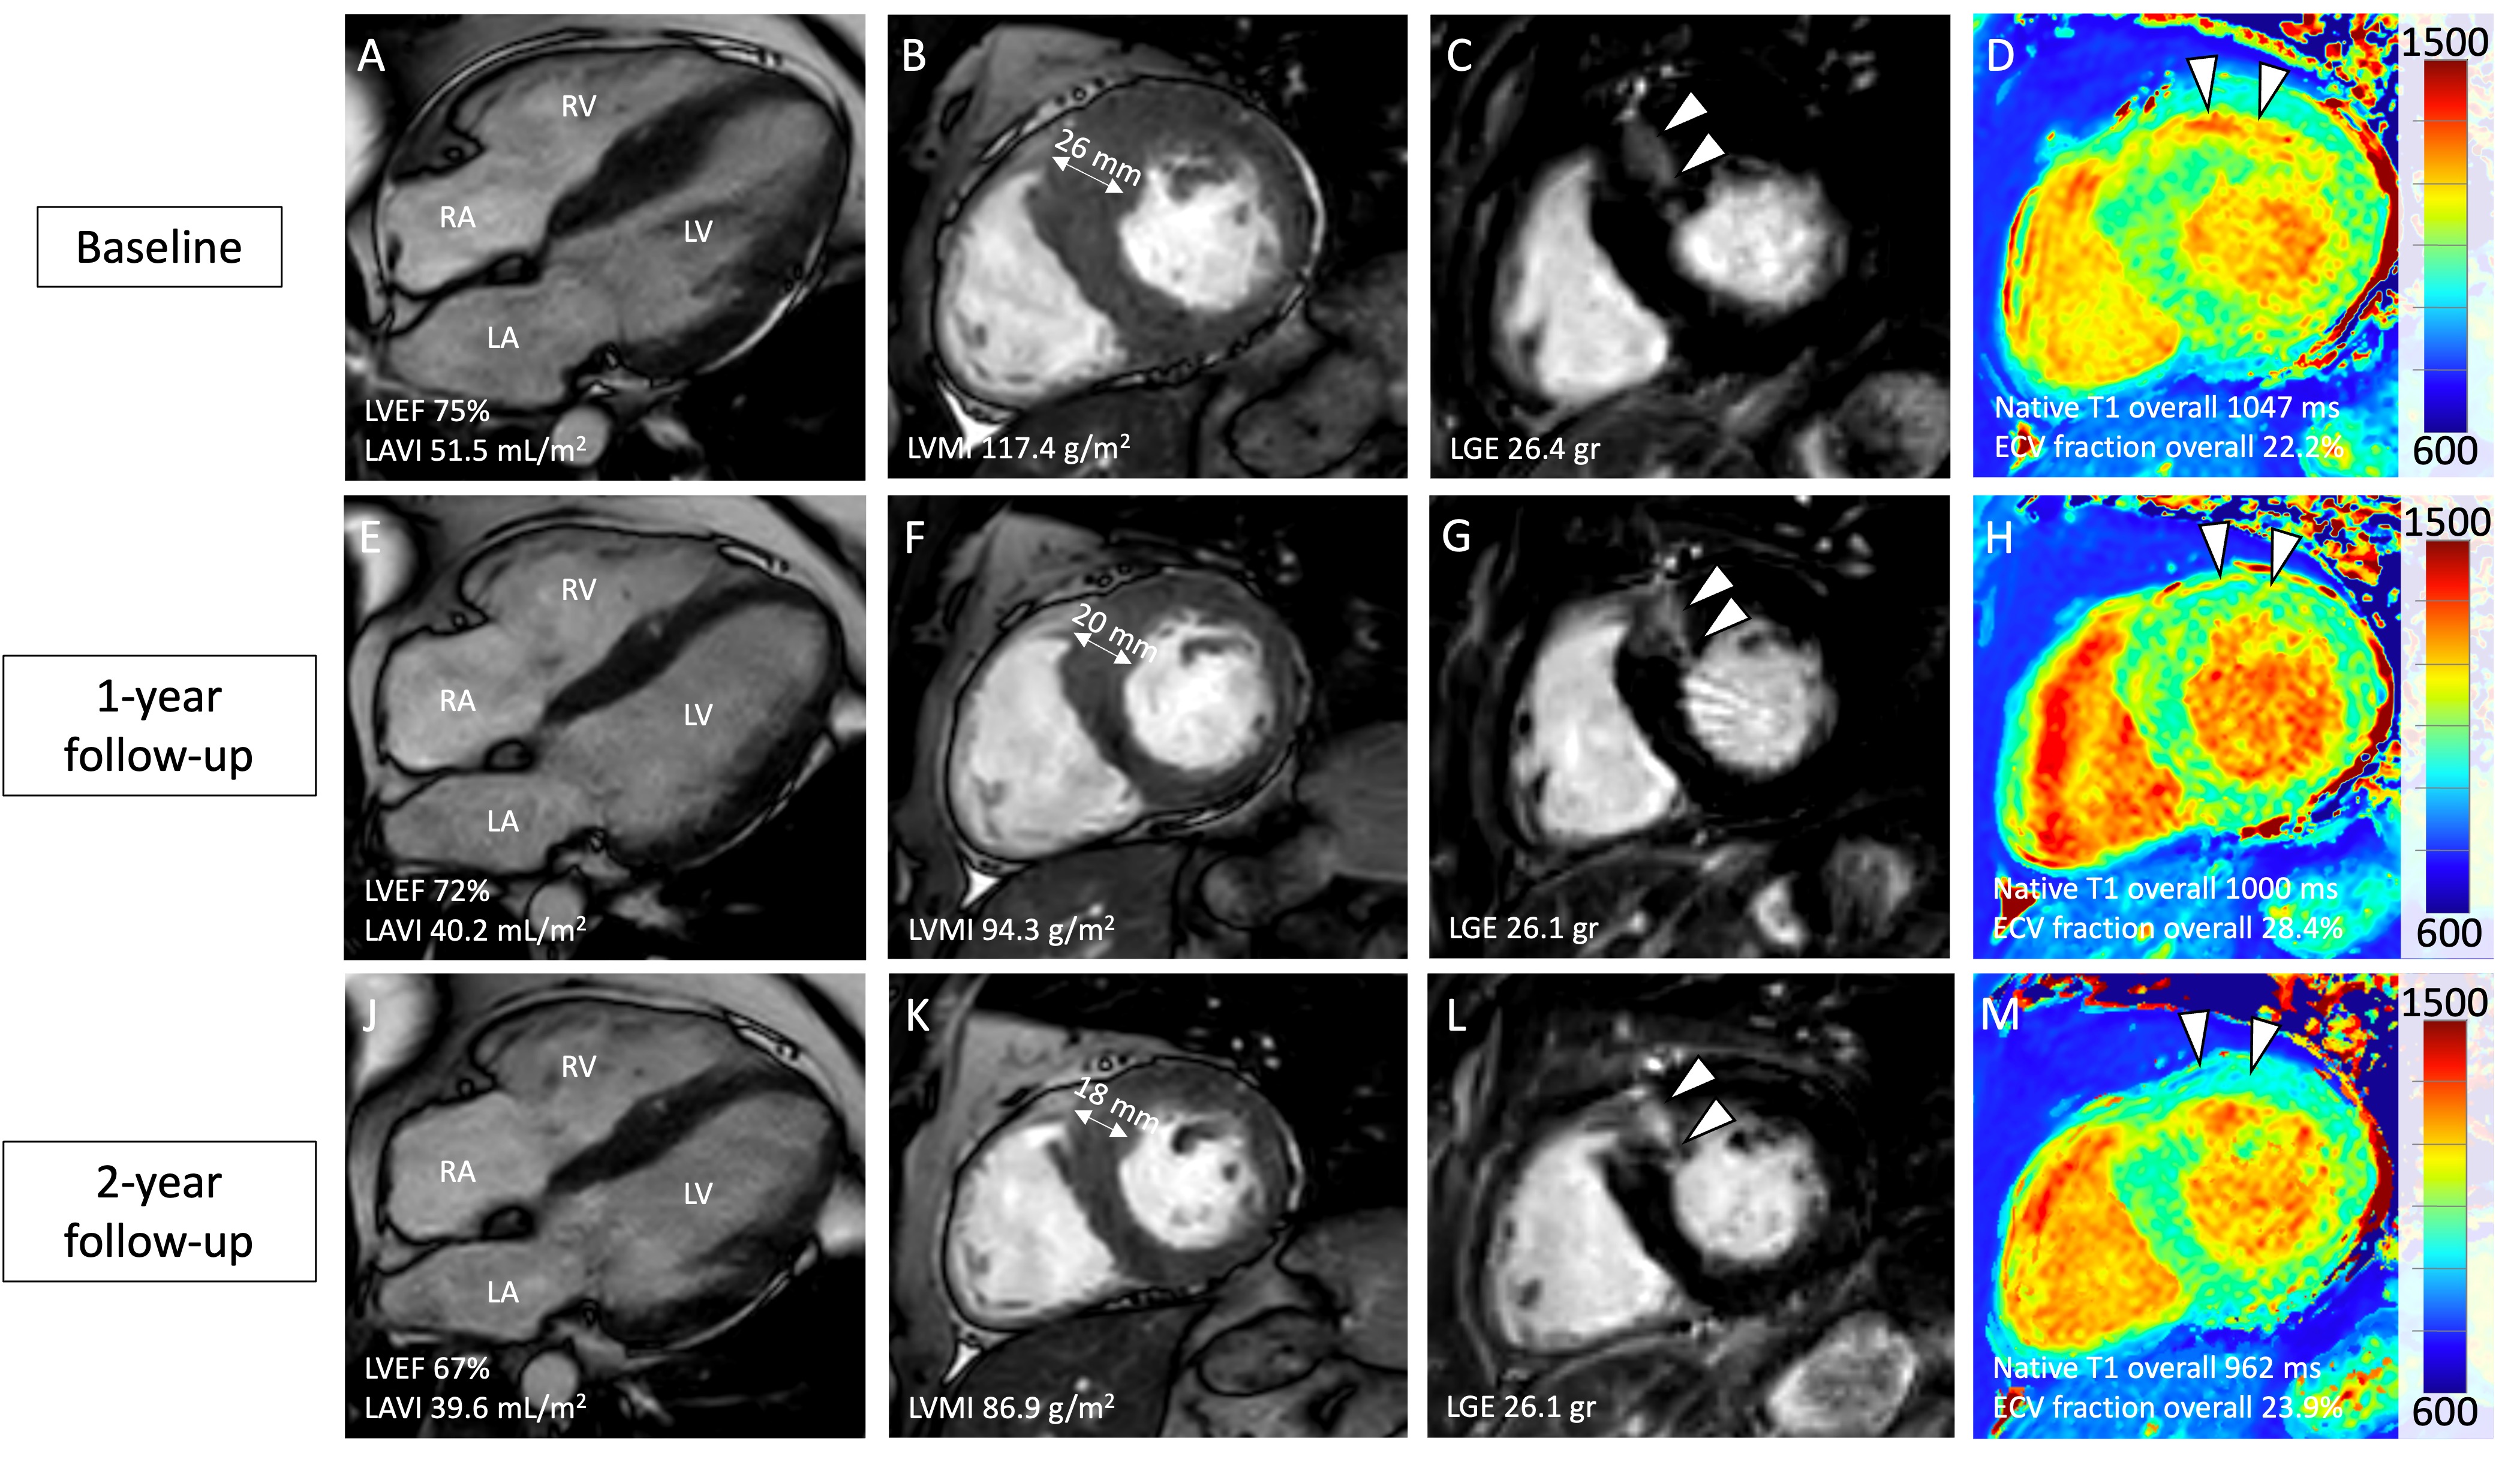

A 39-year-old male with symptomatic oHCM refractory to bisoprolol and disopyramide was initiated on mavacamten therapy. Serial CMR after one and two years demonstrated progressive reverse remodeling over the follow-up period, including ongoing reduction of LV ejection fraction and LV mass index. While late gadolinium enhancement mass remained unchanged, there were divergent changes to measures of interstitial fibrosis: While native T1 relaxation times steadily decreased, extracellular volume (ECV) fraction initially increased but normalized at two-year follow-up.

This case indicates that mavacamten leads to longer-term cardiac remodeling up to two years after initiation of treatment beyond early hemodynamic improvement and reduction of LVOT obstruction. These observations nurture additional studies to investigate longer-term effects on myocardial structure, function, and interstitial fibrosis.